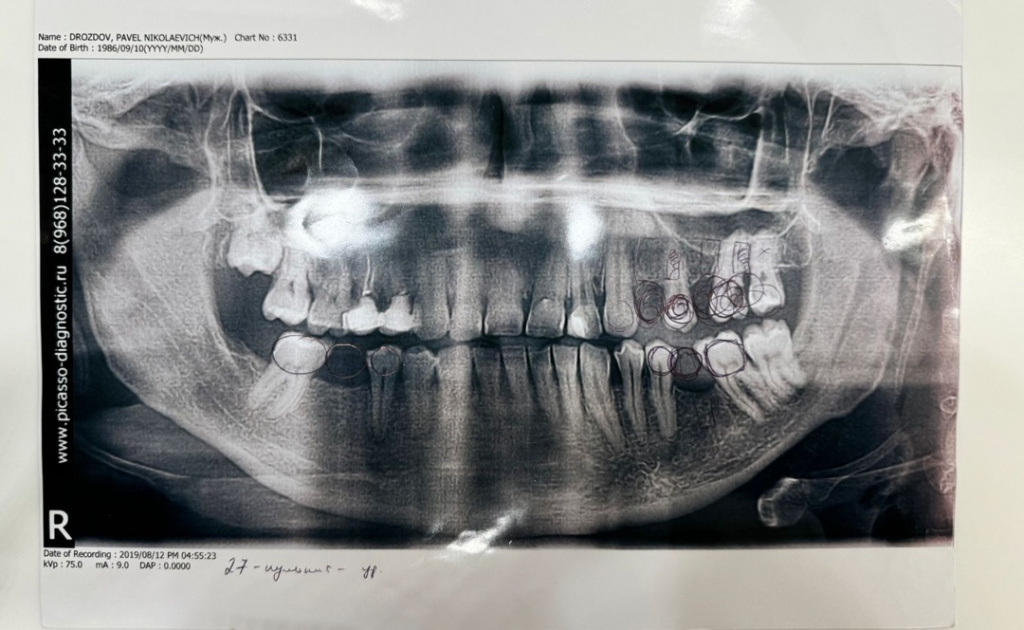

Пациент: Дроздов 10.09.1986

Доктор,первый раз установил имплант UI 3,6*10 классическим протоколом под заглушку с первичной стабильностью 30N.